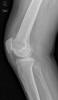

Prótesis completa de rodilla. Situación postquirúrgica. Lateral.

Prótesis completa de rodilla.Lateral.

Prótesis completa de rodilla. Perfil.